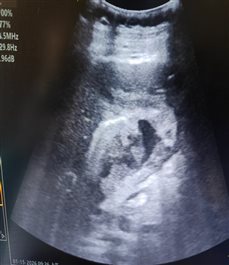

患者女性,72岁,腹痛十余天来诊,胆囊炎病史。超声发现胆囊底部穿孔并肝脓肿形成,范围约8.4×6.5×4.6cm,外科会诊后建议超声引导下穿刺引流脓肿,15日上午由特检科郭连香医师顺利完成肝脓肿置管,引流出脓液约100 ml。患者一般状况良好,安返病房。

穿刺置管引流后,脓腔明显变小。